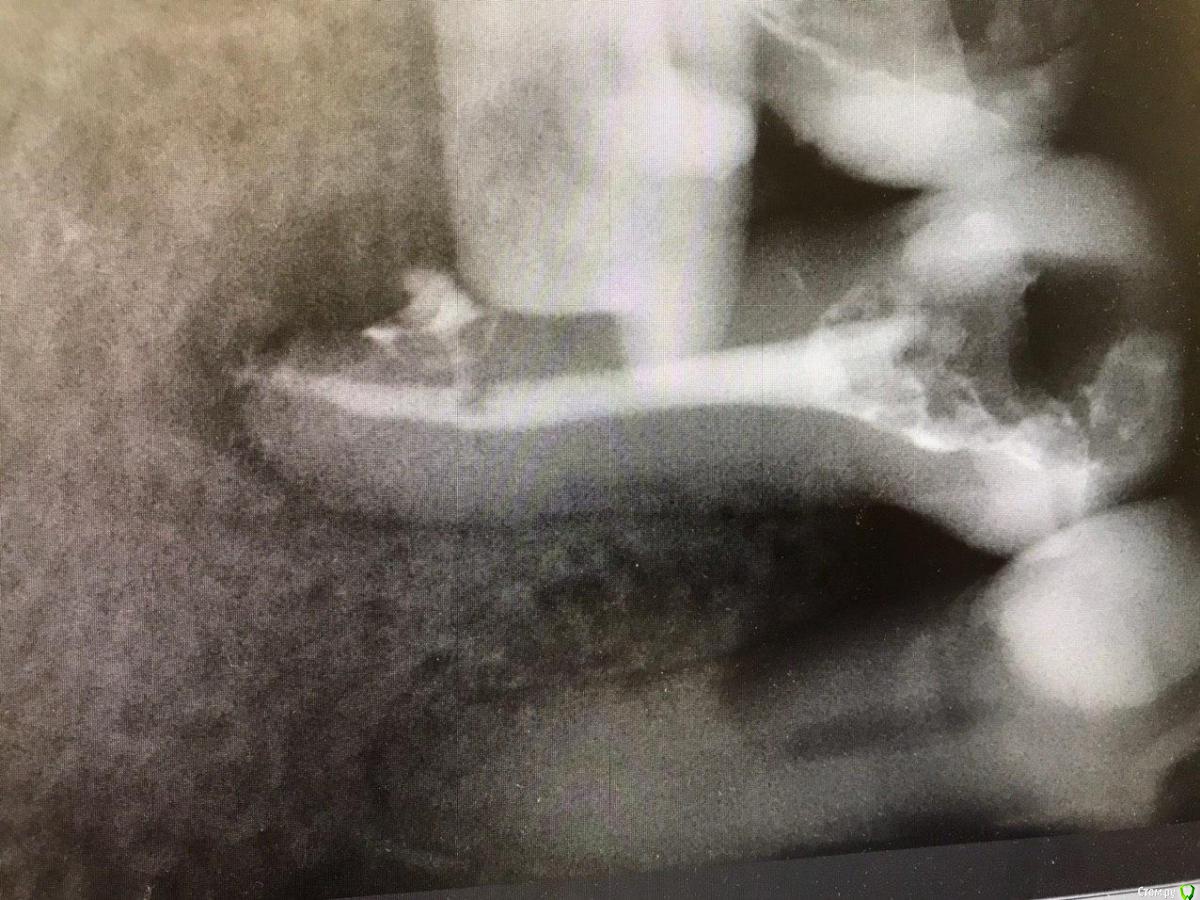

1586Doc Опубликовано 17 мая, 2021 Автор Поделиться Опубликовано 17 мая, 2021 ретрит 46 зуб. Извлечение фрактуры. Дальше будет вкладка и ожидание )) 2 Ссылка на комментарий

Александр23712 Опубликовано 21 сентября, 2021 Поделиться Опубликовано 21 сентября, 2021 (изменено) @1586Doc Фрактура - это трещина. Поэтому "Извлечение фрактуры" немножко режет глаз. *не с целью оскорбить, просто поправка. А работа хорошая. Обработка профайлы? Гидроокись сразу из канюли не страшно вводить? Изменено 21 сентября, 2021 пользователем Александр23712 Ссылка на комментарий

1586Doc Опубликовано 21 сентября, 2021 Автор Поделиться Опубликовано 21 сентября, 2021 10 часов назад, Александр23712 сказал: @1586Doc Фрактура - это трещина. Поэтому "Извлечение фрактуры" немножко режет глаз. *не с целью оскорбить, просто поправка. А работа хорошая. Обработка профайлы? Гидроокись сразу из канюли не страшно вводить? Фрактура - это надлом, перелом)) с немецкого Fraktur — надлом. Обработка профайлы до 30/06. Пару недель гидроокись, потом вертикальная конденсация. Проблем с выводом гидроокиси из канюли никогда не получал. Ссылка на комментарий